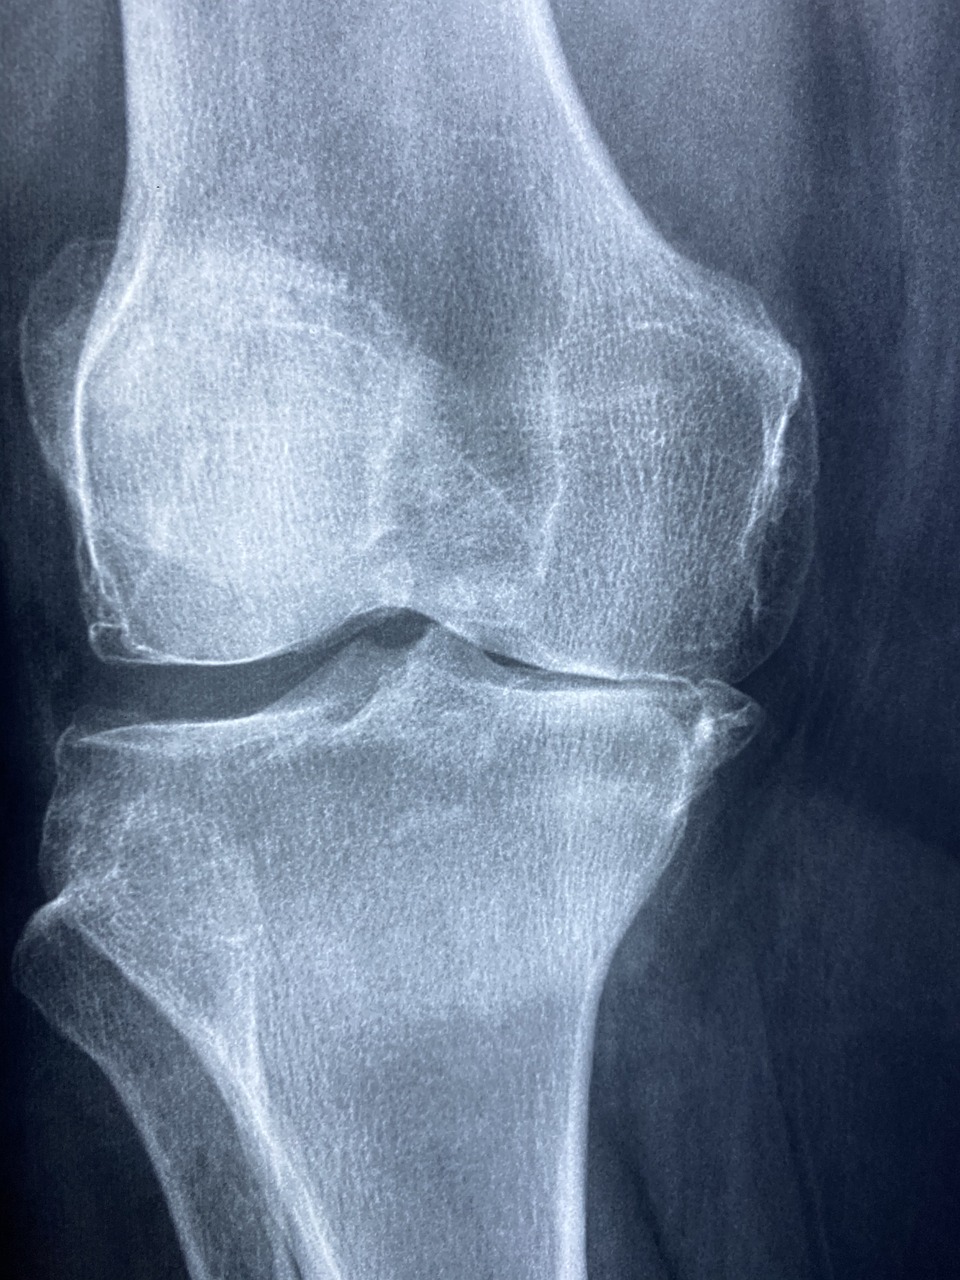

1. 퇴행성 관절염

가장 흔한 무릎 통증 원인입니다.

나이가 들면서 연골이 점차 닳고, 관절 사이가 좁아지면서 통증, 붓기, 관절 마찰음이 발생하죠.

초기에는 무릎을 움직일 때 뻣뻣함만 느껴지지만, 진행되면 앉았다 일어설 때 찌릿한 통증이 동반됩니다.